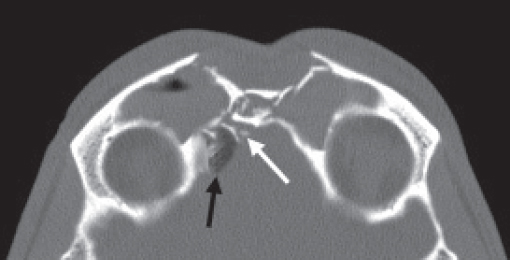

Historically, plain sinus X-rays were used to evaluate facial fractures. Thin cut (1–1.5 mm) axial computed tomography (CT) scans are now the gold standard for diagnosis of frontal sinus fractures. These images are readily reformatted into coronal, sagittal, and threedimensional (3D) reconstructions to improve the diagnostic accuracy. Axial cuts provide excellent information about the anterior and posterior table as well as pneumocephalus ( Fig. 63.5 ). Coronal reconstructions demonstrate the frontal sinus floor, orbital roof, and frontal recess ( Fig. 63.6 ). Sagittal views can assist with evaluation of frontal recess and skull base injuries ( Fig. 63.7 ). Threedimensional reconstructions can be very helpful in delineating the location of bone fragments and reducing the need for excessive dissection intraoperatively ( Fig. 63.8 ). Access to the PACS ( p icture a rchiving and c ommunication s ystem) or some type of presurgical planning software allows the surgeon to manipulate the reconstructions in space, gaining a greater understanding of depth and spatial relationships of the injury ( Video 63.1).